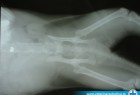

Lečenje mačke pogođene metkom

Ova sirota mačka nekome je mnogo smetala pošto je "zaradila" metak. Iako je metak došao iz vazdušne puške, ta dijabola je bila dovoljno velika da ovog ljubimca dovede na naš operacioni sto. Sva sreća pa je gazda došao veoma brzo i izbegle su se moguće komplikacije i infekcije.